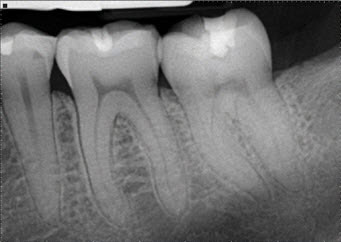

Dental X-Rays With the help of an advanced tool called radiographs, Dental Care Specialists find hidden dental aberrations in dental structures, malignant and benign masses, bone loss and cavities.

Root Canal Treatment Many of you may carry a misconception about root canal treatment that it is a painful procedure, however, you will fret less once you understand why root canals are done. The removal of infected soft tissue within a tooth, and replacing it with a new artificial inert filling like material is a standard root canal procedure.

If the following problems persist, you are in ardent need for a root canal treatment.

• constant ache in tooth

• Tooth decay or extensive cavities

• Teeth darkening, possibly after a serious injury or trauma

• Gum swelling near tooth

• Sensitive gums or teeth

• Tooth fractureh